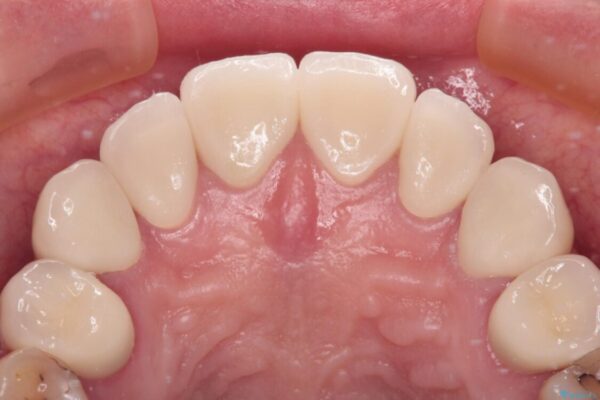

治療後

• むし歯だらけの前歯をオールセラミッククラウンできれいに 治療後画像

治療後について

歯肉移植術による根面被覆を行うかどうかは非常に悩まれていましたが、歯肉が覆われたことで長く見えていた歯の長さが整い、きれいな前歯の仕上がりとなりました。